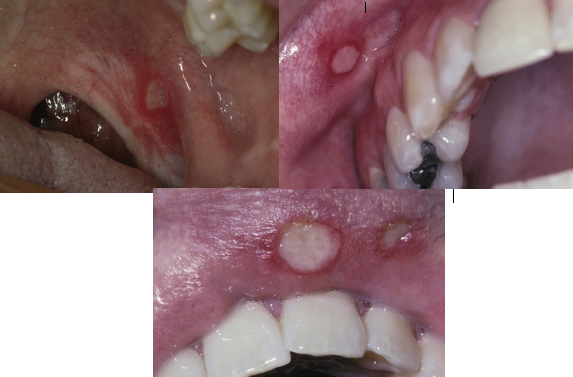

recurrent aphthous ulceration - minor

how do RAU minor lesions present?

erythematous macule followed by a central yellow-white, removable fibrinopurulent membrane

ulcerations are less than 1cm

RAU minor lesions heal without scarring in what time frame?

1-2 weeks